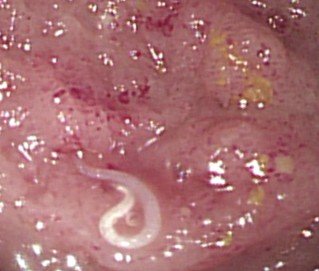

示意圖。圖片來源 / medicszone

誰知這一照,許秉毅醫師驚見患者大腸不僅有多處紅腫,還有超多隻鑽來鑽去的白色蟲蟲!「噁心死了!天啊!居然是久違的『鉤蟲』,我已經20多年沒見到它的蹤跡了!」好在患者在服用驅蟲藥後,已經沒有腹瀉症狀,事後也透露自己是在中秋節吃完烤肉後才開始拉肚子,懷疑是烤肉被汙染。